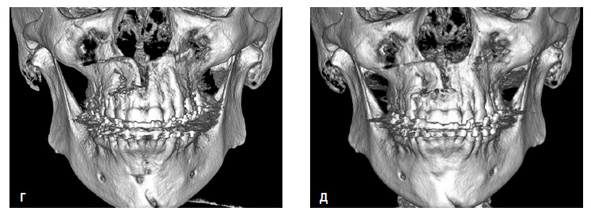

Рис. 11. Пациент Б. 47 лет. Ds: СЗЧЛА, дистальный прикус, сужение верхней и нижней челюстей. Исследования конусно-лучевой компьютерной томограммы, аксиальный срез в области альвеолярного отростка верхней челюсти: а – до операции, б – контроль в день операции, в – контроль при получении достаточного расширения (1 месяц), г – контроль созревания костного регенерата перед снятием аппарата (4 месяца), д – контроль через 10 месяцев с момента операции